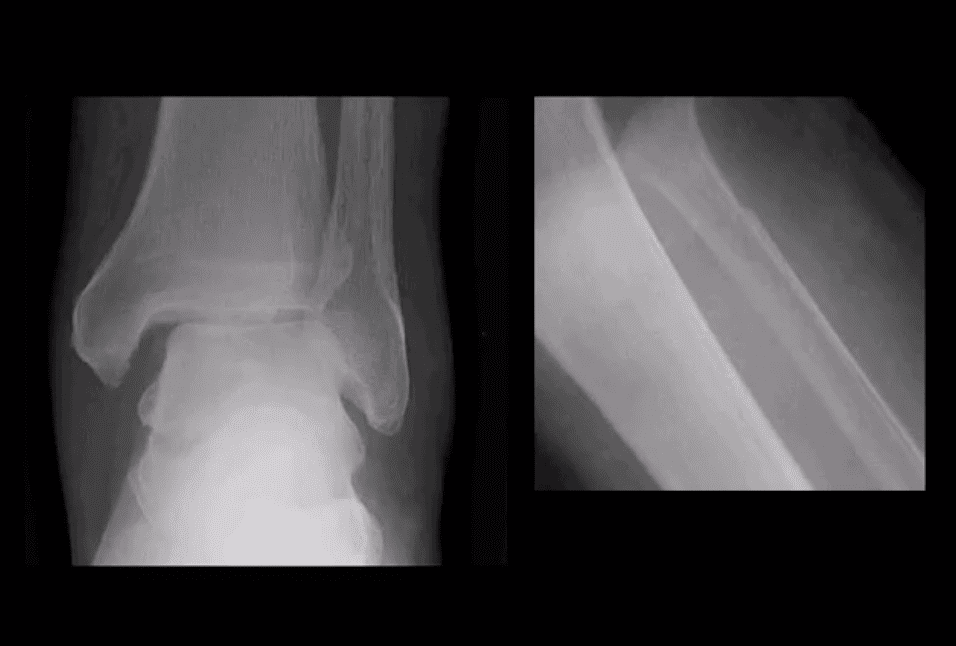

Calcaneal Fracture

- Most frequent tarsal Fx. 17% open Fx

- Mechanisms: axial loading (intra-articular Fx into sub-talar and calcaneal-cuboid joints in 75% cases). Avulsion by Achilles tendon (m/c in osteoporotic bone). Stress (fatigue) Fx.

- Intra-articular Fx carries a poor prognosis. Typically comminuted. Rx: operative.

- B/I calcaneal intra-articular fx with associated vertebra compression Fx with associated vertebral compression Fx (T10-L2) often termed Casanova aka Don Juan (Lover’s) fx.

- Imaging: x-radiography with added “heel view” 1st step. CT scanning is best for Dx and pre-op planning.

- Radiography: Bohler’s angle (<20-degrees) Gissane angle >130-degrees. Indicate Calcan, Fx.